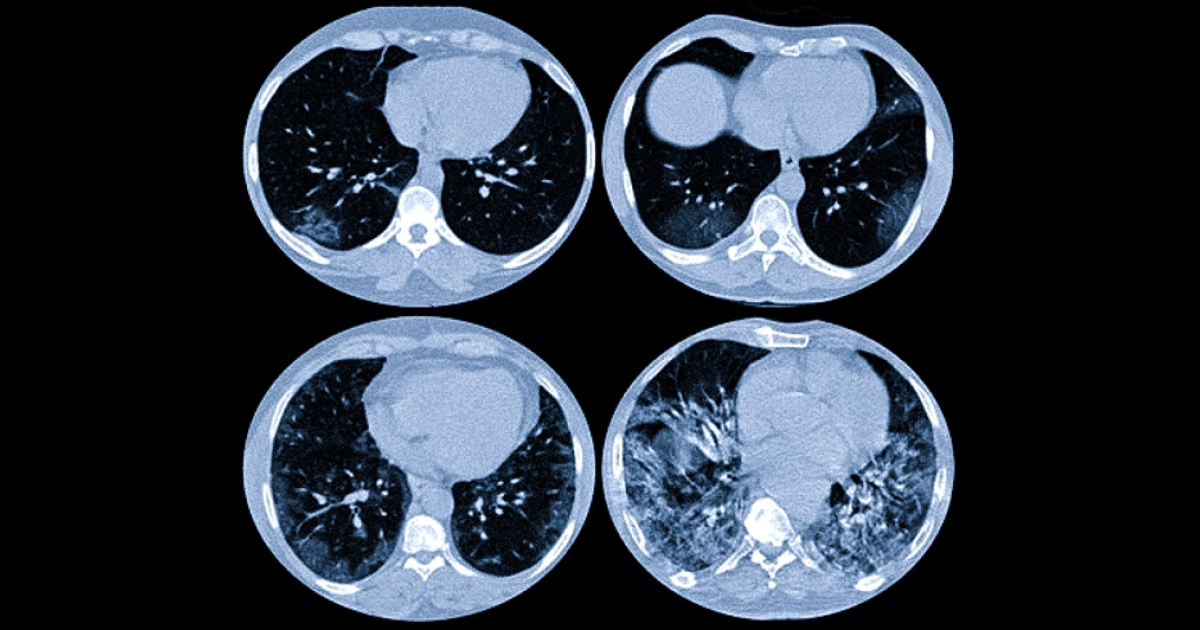

Комп’ютерна томографія легень — один із найточніших методів оцінки стану легеневої тканини. Саме КТ дозволяє виявити зміни, які часто не видно на звичайній рентгенографії. Однак для пацієнтів висновок радіолога може виглядати складним і незрозумілим: у ньому зустрічаються такі терміни, як «матове скло», «консолідація», «ретикуляція» або «фіброзні зміни».

Термін «матове скло» (ground-glass opacity) означає ділянку легеневої тканини з підвищеною щільністю, через яку все ще видно судини та бронхи.

Головна особливість «матового скла» — часткове збереження повітряності легені. Саме тому на КТ просвічуються судини.

Консолідація: більш щільні зміни

Це ділянка легені, де повітря в альвеолах повністю заміщується рідиною, клітинами запалення або іншими тканинами. На КТ така зона виглядає значно щільнішою, ніж «матове скло».

На відміну від «матового скла», при консолідації судини та бронхи можуть бути погано видимими або зовсім не визначатися.

Що таке ретикуляція

На зображенні це виглядає як тонка сітка або мережа.

Дифузні зміни в легенях

У висновку КТ можна зустріти фразу «дифузні зміни». Це означає, що патологічний процес поширюється не на одну локальну ділянку, а охоплює значну частину легеневої тканини або обидві легені.